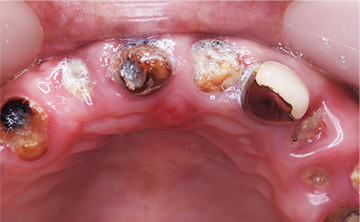

虫歯を放置して3年経って来院された患者さんです。噛めなくなったが主訴です。虫歯が進行しているのも確かですが、歯石も多く付着していますね。虫歯の中にオレンジのものが見えていますが、これは、根の治療後に詰める防腐剤ですね。

根の治療をすると歯に痛みを感じなくなるので、虫歯が進行しても痛みを感じずに歯冠崩壊を招きます。できるだけ歯の神経を取らない方が良いですが、虫歯が歯の神経に近く痛みが出る場合は、虫歯の歯の神経治療が必要になります。

非常に素晴らしい患者さんで、この後、しっかりと通って虫歯を全て治して、噛める状態にまで回復しました。

虫歯を放置して10年くらいの症例です。お口の中には、上あごは、一本しか歯が残っておらず、全く噛めないということで来院された患者さんです。痛い時期はどのようにして過ごされたのかと聞くと、とにかく痛み止めとお酒で痛みをごまかして過ごされたそうです。